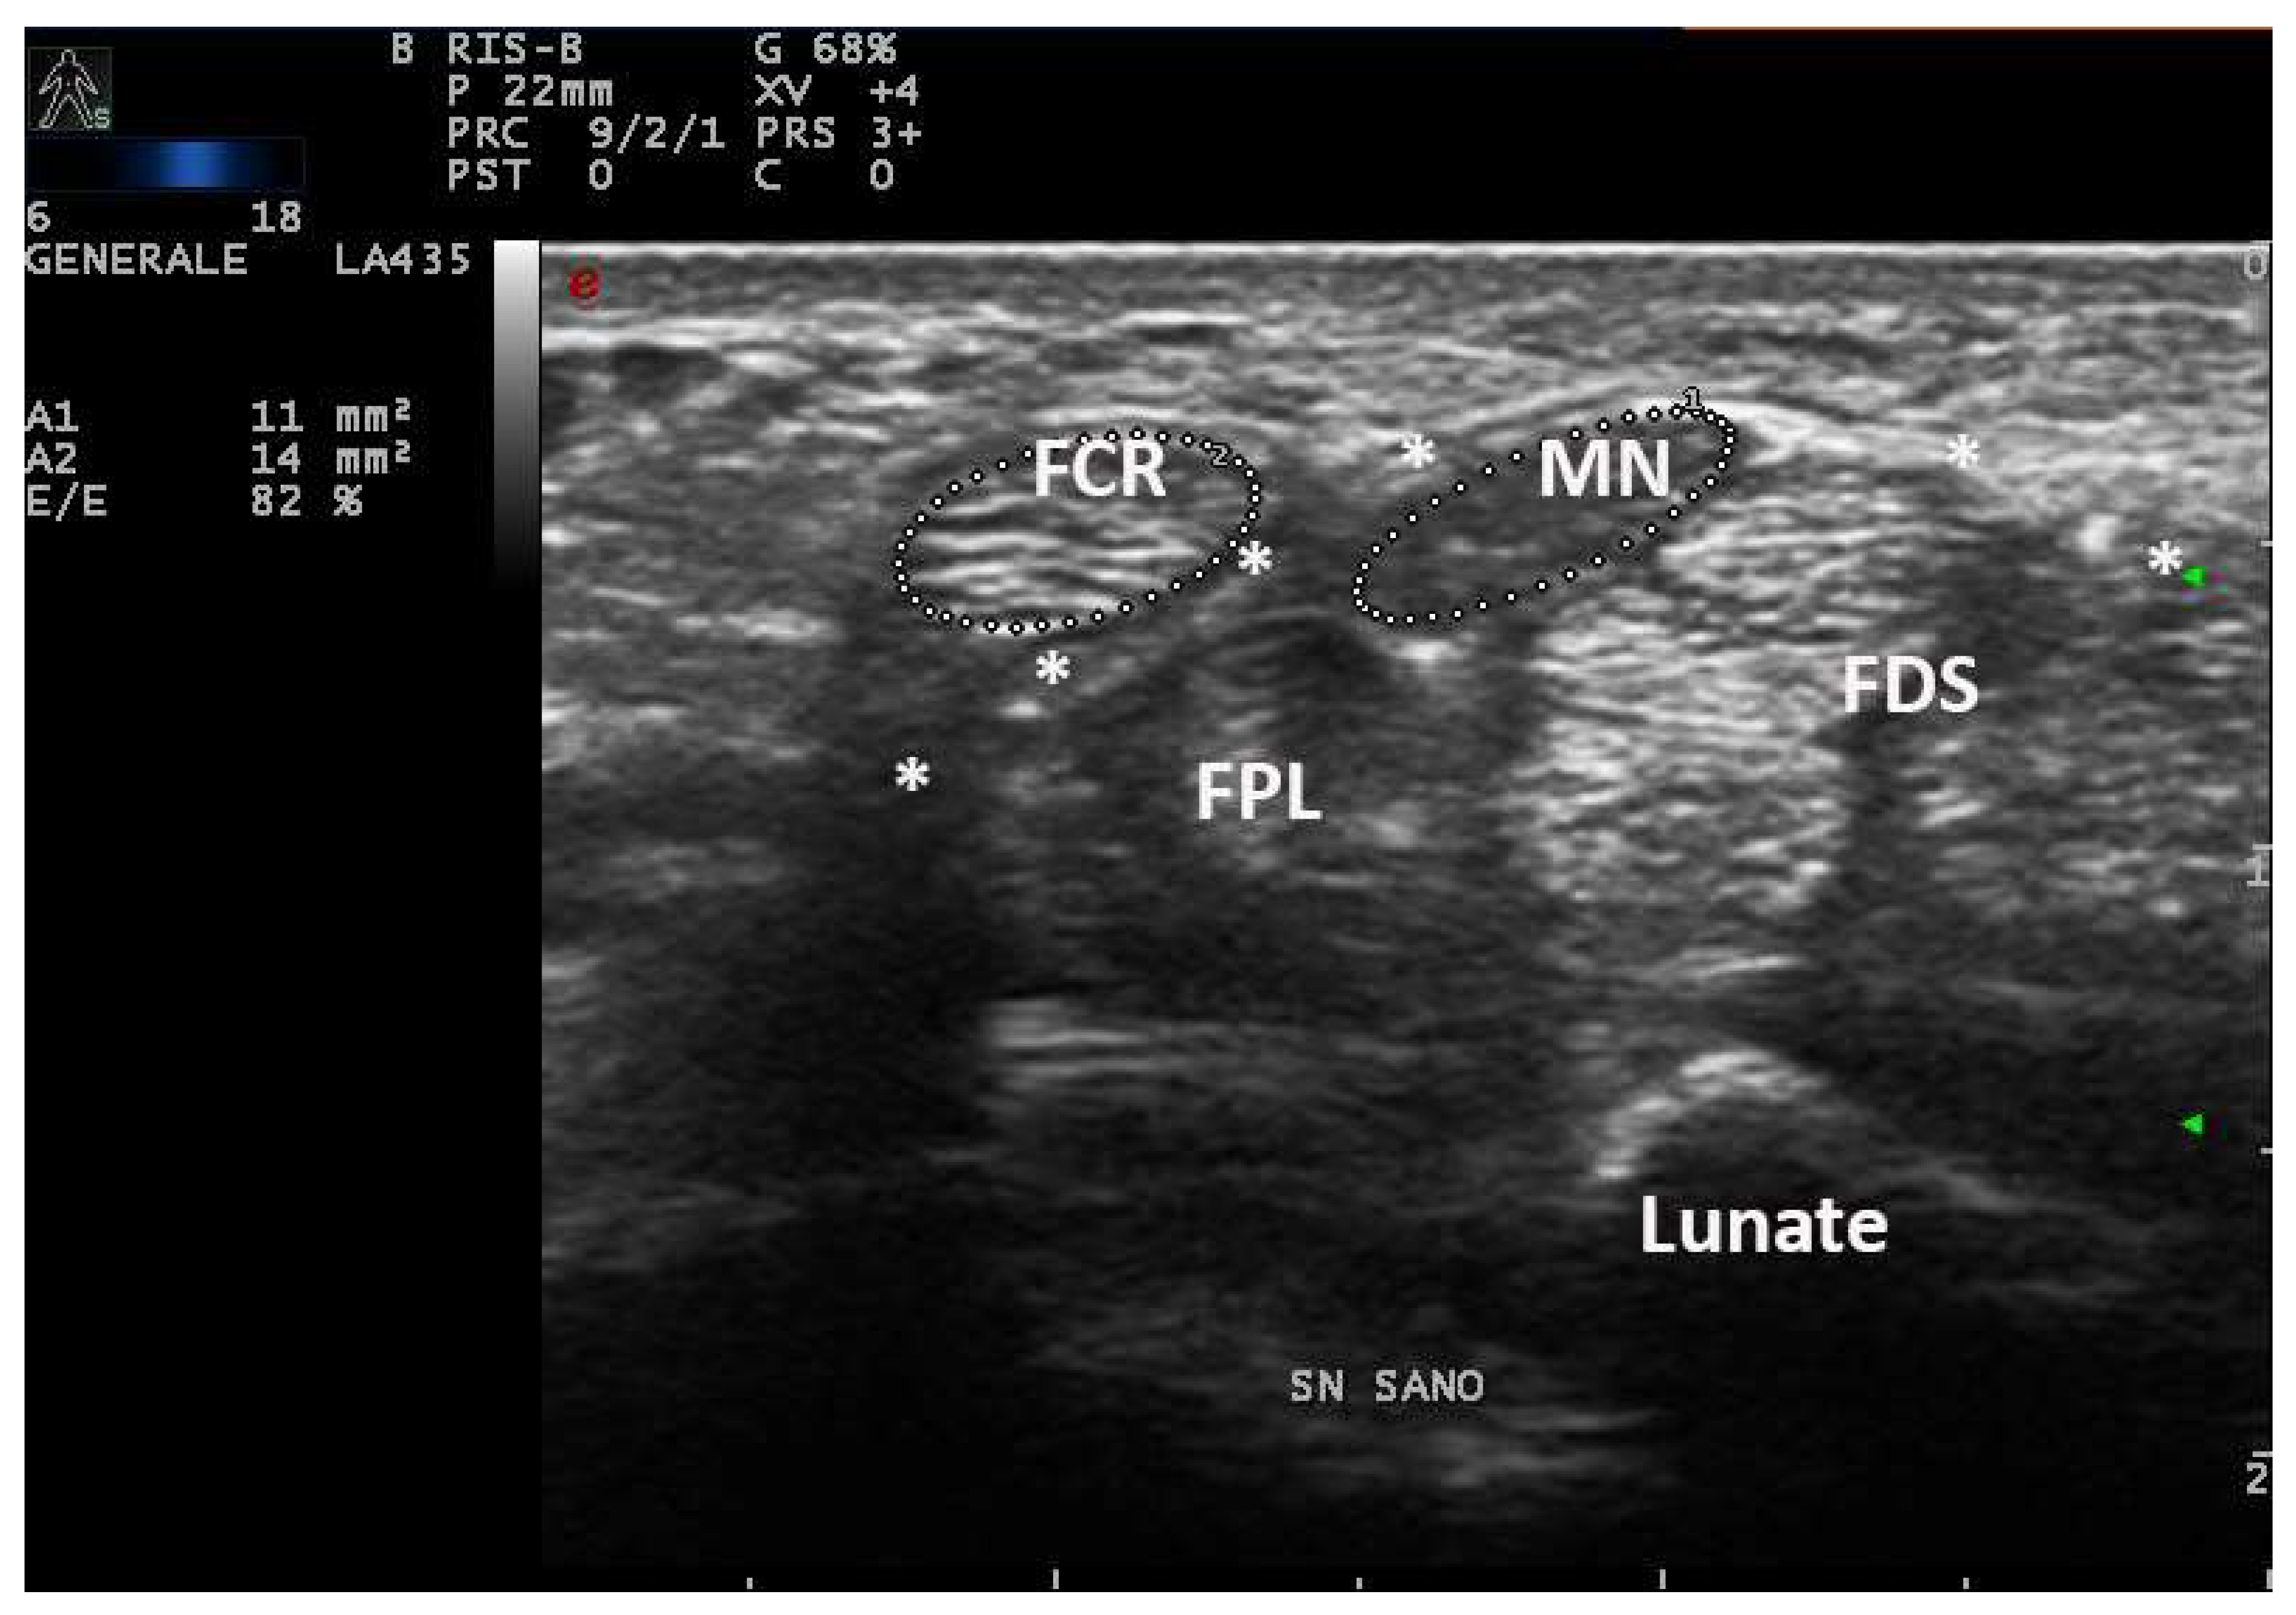

In fact, an earlier study showed a positive correlation between CSA and wrist circumference, height and weight [5]. For these reasons, smaller people have lesser wrist circumference and lesser CSA of the median nerve also in pathologic conditions. On the other hand, taller subjects can have MN-CSA over cut-off in the absence of compressive neuropathy (Figure 1) [16].

Figure 1.

Transverse scan over left carpal tunnel of a tall male, asymptomatic for CTS in left hand (180 cm × 85 kg, 19 cm of wrist circumference). Linear 6–18 MHz probe. The MN-CSA (area 1) results of 11 mm2 are suggestive of pathologic swelling, but EDS was normal (PS = 0, performed as control side, for CTS in the right side). The flexor carpi radialis (FCR) shows a CSA (area 2) of 14 mm2. MN = median nerve, FPL = flexor pollicis longus, * = transverse ligament, FDS = flexor digitorum superficialis.